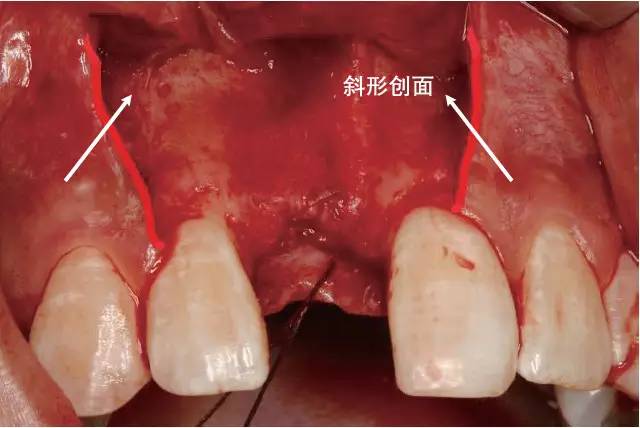

牙周病学 第四版 10ppt 内斜切口的步骤(以改良widman翻瓣术为例) (1

牙医学堂组织切口与瓣的设计翻瓣术切开步骤口腔种植手术学图解